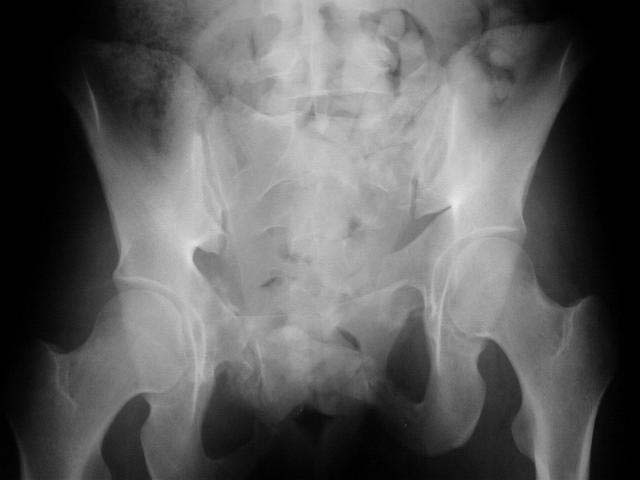

2 days ago I was asked by a local rehab hospital to evaluate a 21 yo female who while visiting out of town was thrown from a walk bridge (fall 20-30 ft). She sustained a left sided lateral compression pelvic ring injury and a fracture dislocation of the left elbow. The injury occurred on 9/1/01 and the treatment of her pelvic injury was skeletal traction and the elbow was splinted only (now subluxed with a comminuted radial head fracture and no motion). Her elbow is a priority a will be addressed.

Probably the best treatment is avoiding this situation. Educate the individuals involved in her initial evaluation. Teach them the importance of clinical and radiographic patient evaluations. Teach them exactly how to examine an injured pelvis. If it had been examined initially, the clinical instability would have been obvious. The radiographs reveal bilateral, comminuted, displaced anterior ramus fractures along with a sacral fracture which violates the anterior, middle, and posterior portions of the sacrum (analogous to a complete sacroiliac dissociation)....a "3 column injury"(if you pretend that the sacrum is a vertebra), so to speak.